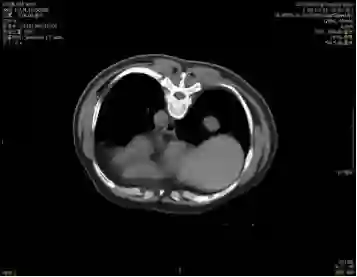

5. 2017-9-5广东省人民医院PET提示:右肺下叶肿物2.8*2.7cm,SUV 22.3,双侧颈部、双侧气管旁、隆突下、食管旁、右侧肺门淋巴结肿大,代谢升高,考虑为转移灶,右侧肾上腺转移灶,具体结果见下图:

7.目前诊断:右下肺肿瘤cT1cN3M1c IVB期(颈部淋巴结、肾上腺)

2.  根据PET/CT目前诊断为右下肺肿瘤cT1cN3M1c IVB期(颈部淋巴结、肾上腺)